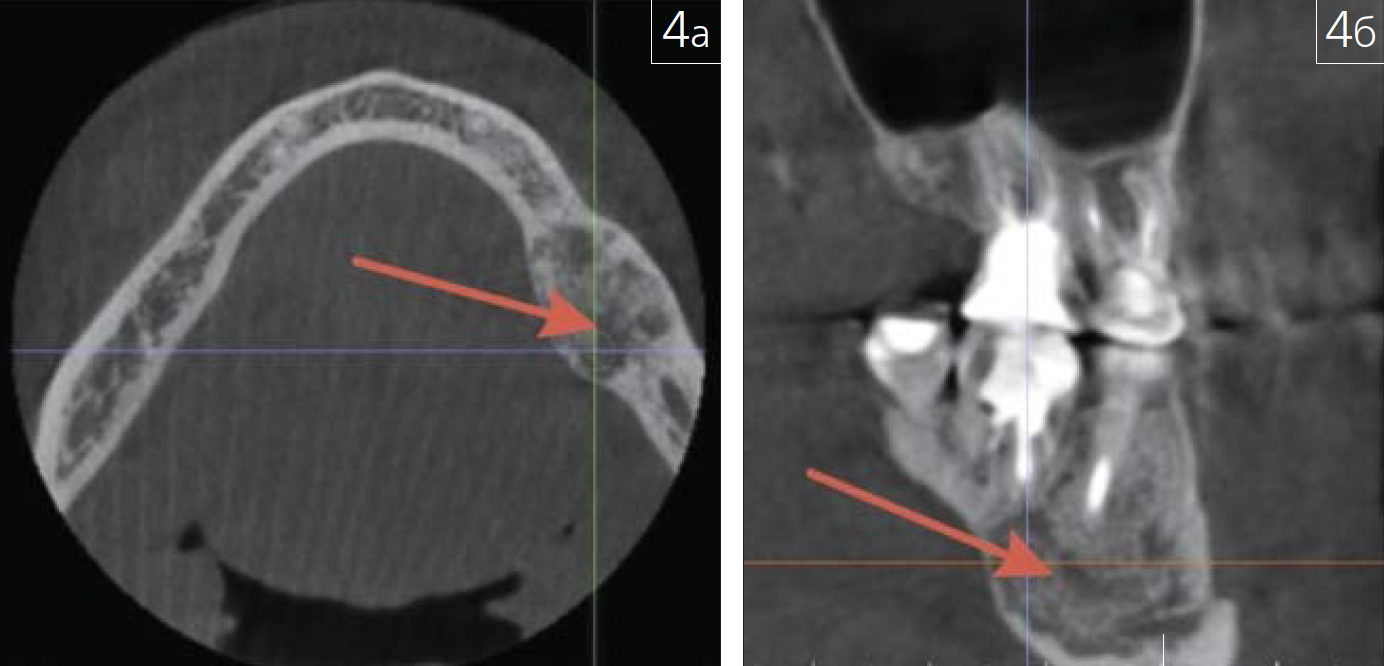

фиброзной дисплазии (рис. 4 а-в; 5),

Рис. 4. Фиброзная дисплазия нижней челюсти слева(показана красными стрелками) на КЛКТ: а – аксиальная проекция;б – атипичная косая проекция

Рис. 5. Участок цементно-фиброзной дисплазии в областикорня 3.4 зуба (показан красной стрелкой) на КЛКТ: плоскостнаяреконструкция в сагиттальной плоскости

которая может быть семейнонаследуемой, а основным рентгенологическим критерием оценки является сохранность замыкательной пластинки, свидетельствующая о доброкачественности патологического процесса.